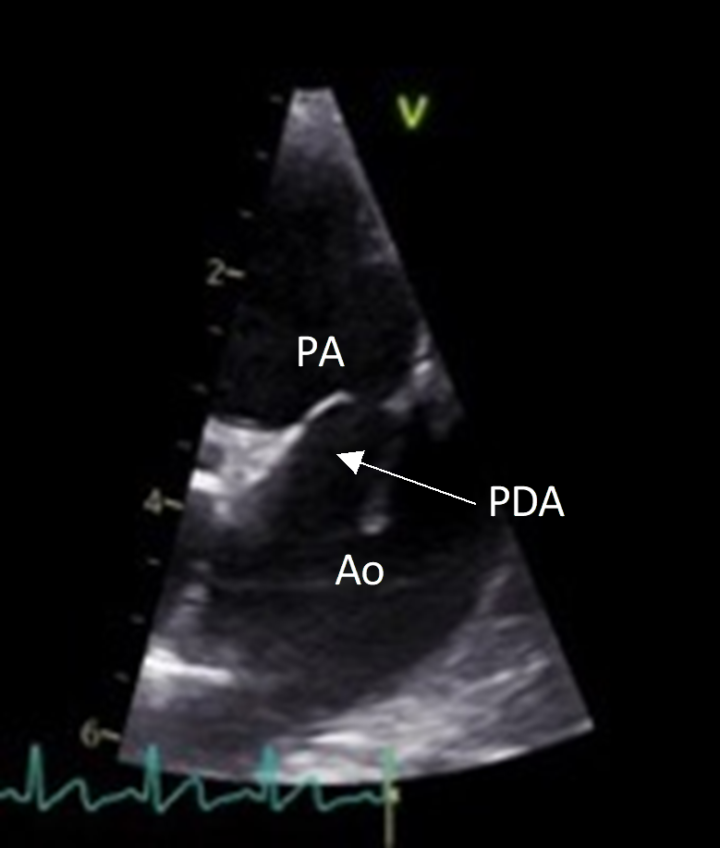

Due to its characteristic murmur, the index of suspicion for an uncomplicated (“left-to-right”) PDA may be high from physical exam findings alone; however, a definitive diagnosis requires echocardiography. The ductus can typically be visualised entering the pulmonary artery (Figure 1), and continuous flow through the duct is apparent on spectral Doppler imaging (Figure 2). Left-sided cardiomegaly may also be apparent.

Occlusion of PDA can be achieved by surgical thoracotomy with extra luminal ligation or via minimally invasive techniques. Interventional occlusion of PDA using a specialised device called an Amplatz Canine Ductal Occluder or “ACDO” (Figure 3) has been well described in veterinary medicine (Gordon et al., 2010).